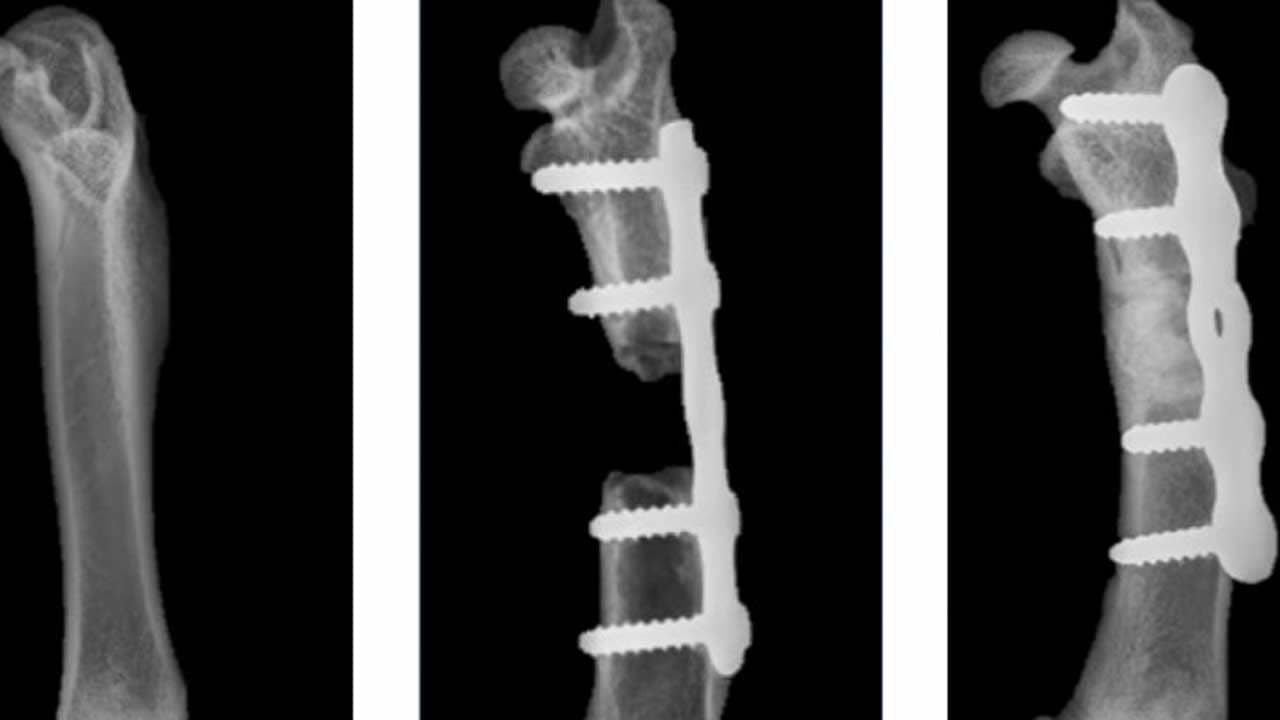

আসলে দু রকম রাসায়নিকের মিশ্রণ দিয়েই তৈরি হয়েছে এই ক্ষত সারানোর উপায়। ওই মিশ্রণ ইনজেকশনের মাধ্যমে ক্ষতিগ্রস্ত অংশে প্রবেশ করাতে হবে। আর তাতে হবে ম্যাজিক! আবার তৈরি হবে হাড়, পূরণ হবে ক্ষত। আসলে হাড় তৈরি হবে না। হাড়ের মতো একটা কৃত্রিম জিনিস গঠন হবে ওই ক্ষত স্থানে। অধ্যাপক অশোক কুমার জানিয়েছেন, কৃত্রিম এই হাড় হবে স্বাভাবিক হাড়ের মতোই। ভারতের চিকিৎসা বিজ্ঞানে এটা বিপ্লব আনতে পারে বলে মনে করছেন তিনি। গত বুধবারই এই ওষুধ বিক্রির জন্য এক বেসরকারি সংস্থার সঙ্গে স্বাক্ষরিত হয়েছে চুক্তি।

অধ্যাপক অশোক কুমার জানিয়েছেন, ওই ফ্লুইড শরীরে প্রবেশ করার ১৫ মিনিটের মধ্যেই জমে শক্ত হয়ে যাবে। তবে এর ফলে রক্তে অক্সিজেন সঞ্চালনের ক্ষেত্রে কোনও সমস্যা হবে না। ফলে ক্ষত সারানোর যে স্বাভাবিক প্রবণতা শরীরের মধ্যে থাকে, তাও ব্যহত হবে না।

মূলত টিবি ও বোন ক্যান্সারের রোগীদের ক্ষেত্রে এই উদ্ভাবন উপকারী হবে বলে মনে করছেন ওই অধ্যাপক। তিনি জানান, ওই সব রোগীদের ক্ষেত্রে ক্ষতিগ্রস্ত অংশ বাদ দিয়ে দেওয়া ছাড়া কোনও উপায় থাকে না। আর ওই অংশে নতুন করে হাড় তৈরি হওয়ার কোনও আশাও থাকে না। অনেক সময় দুর্ঘটনায় আহত হলেও একই সমস্যা হতে পারে। এ ক্ষেত্রে চিকিৎসক নতুন পদ্ধতি ব্যবহার করতে পারেন। এতে কোনও ইনফেকশন হওয়ার সম্ভাবনাও নেই।